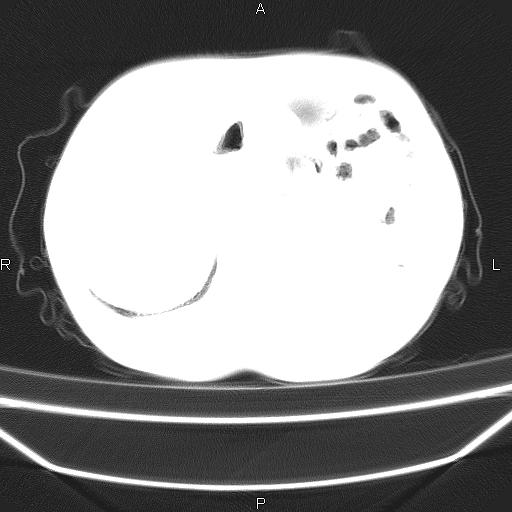

患者,男。50岁。近几日有咳嗽症状,无其他不适,既往病史无,考虑膈疝。请前辈们看看指导指导。

膈膨升,左下肺通气不良,膈肌好像还完整。

考虑左侧膈疝。

左侧膈疝。

符合隔膨升,膈肌较完整。